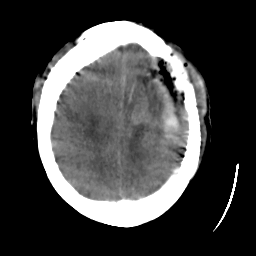

Meningioma: Roentgen-ray CT #1 -- Slice #17

[Home][Help][Clinical] Slice 17